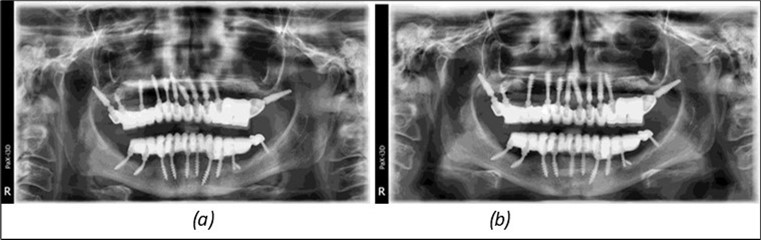

Figure 14.Rx panoramic final situation control: (a) Panoramic X-ray with the addition of a distal BCS implant in quadrant 3 at 11.2022; (b) Control X-ray, 10.2023.

The results of rehabilitation treatment with corticobasal and compressive implants with a polished surface after the failure of two stage implants were highlighted over a period of 3 years and 3 months as being very good (Figure 14, Figure 15), with the patient completing a satisfaction survey in this regard. Certainly, it is necessary to continuemonitoring these results in the long term.